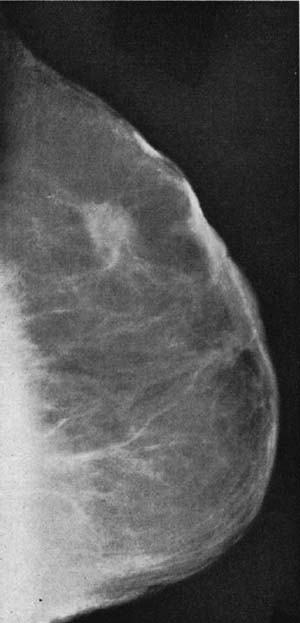

図7. マンモグラフィー,斜位像(乳癌).専用装置を使用していないことを考えると十分高画質であるといえる.[13].

【要旨】 M. D. Anderson病院の乳腺専門施設で,3年間に撮影したマンモグラフィー1,000例について検討した.撮影方法は,頭尾,斜位,腋窩の3枚で,年齢や乳腺の状態に応じて22~28kV,300mA,6秒.悪性を示唆する所見は,微細な石灰化,不均一な濃度の腫瘤,不規則な棘状輪郭,周囲の二次性変化(皮膚皮溝,乳頭陥凹)などである.乳癌は245例で,このうち238例は悪性と診断できた.また触診で正常,X線でのみ診断できた症例が19例あった.

【解説】 1930年代から始まった乳腺のX線検査は,技術的にもそれなりに進歩して所見に関する知見も蓄積したが,触診を主体とする臨床診断に対する有用性については明らかなデータがなく,外科医の中にはその意義について否定的な意見も少なくなかった.そのような状況の中,1960年に発表されたこの論文は,1,000例という十分な症例数に一貫した検査を行ない,正常例,明らかな良性疾患以外は,全例に組織診断を得て,悪性疾患の正診率99%という圧倒的な成績を示して,X線検査の有用性を明らかにして,その後の方向性を決定づけた記念すべき論文である.

この論文には実際の写真が掲載されていないが,1963年の論文に掲載されている同じ撮影法による写真をみると(図7)[13],専用装置を使わず,圧迫法もグリッドも使用していないにもかかわらず,非常に高画質であることに驚かされる. なおマンモグラフィー(mammography)という言葉を,乳腺X線撮影に対して初めて使用したのもこ論文である (1937年にHickenが使用しているが,これは乳管造影をさしていた[6]).